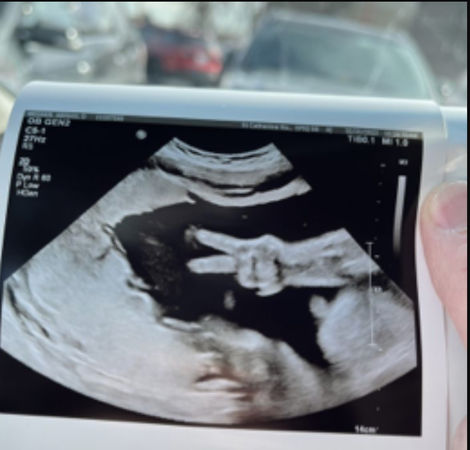

妈妈产检胎儿突然比YA 奇迹超音波照曝光

刚怀孕的新手爸妈最期待的,莫过于产检时的超音波照,美国就有一名产妇在进行产检时,当医生在进行超音波检查时,宝宝竟突然伸出手比YA,让医生也吓了一大跳。

住在印第安纳州的艾比(Abby Weener)正怀著第三胎,她7日和丈夫维纳尔一起到医院进行产检,当医生进行超音波检查时,31周大的胎儿竟突然伸出手比YA,让医生吓一大跳,在场的人也全都笑了出来。

凯尔表示,“在场医护人员说他们从未见过这样的事情,这是非常独一无二的。”虔诚信仰基督教的夫妻也认为,这是上帝送给他们最棒的礼物之一。